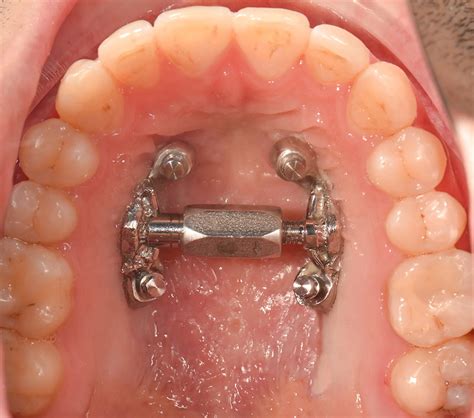

- Expansor asistido por microtornillos (MARPE): Es una variante para pacientes más mayores. En este diseño, el expansor incorpora pequeños tornillos de titanio que se anclan directamente al hueso del paladar.

El tratamiento dental tradicional para resolver este problema es la cirugía Ortognática: una expansión rápida a través de una cirugía maxilar. En los últimos años ha aparecido una innovadora técnica llamada MARPE (Microimplant Assisted Rapid Palatal Expansion), basada en el anclaje de un expansor a través de microtornillos en el paladar.

Esta técnica nos permite aplicar las fuerzas necesarias para expandir el maxilar sin tener que aplicar fuerzas en los dientes del paciente. En los casos en que el hueso sea muy duro (hombres mayores de 30 años y mujeres mayores de 40 años), es posible que sea necesario realizar una cirugía complementaria para ayudar al aparato a realizar la expansión.

Una vez fabricado el aparato, en la consulta se fijará el expansor en el paladar a través del anclaje de los microtornillos guiados según la planificación digital. Después de la colocación del expansor en el paladar, el propio paciente lo activará todos los días durante un periodo aproximado de entre tres y cuatro semanas y según las recomendaciones del ortodoncista.